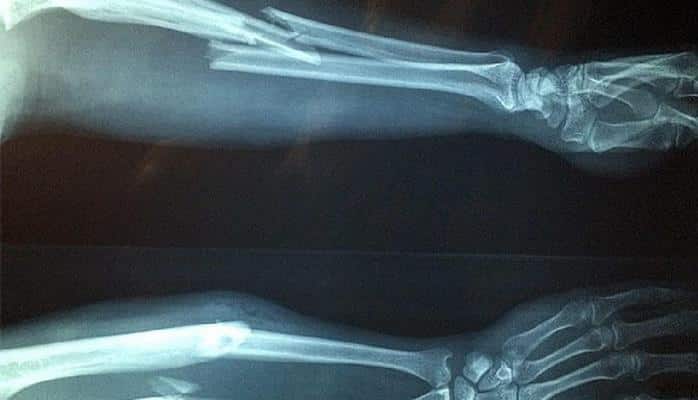

Теперь лечение переломов может занять пару недель, а не месяцев, как при традиционной терапии.

Исследователи из Стэнфорда "вывели" отдельный тип стволовых клеток, отвечающих за укрепление костных образований, пишет Engadget. Перебор особенностей экспрессии генов с помощью машинного обучения позволил учёным выявить отдельные типы клеток, способных восстанавливать поражённые участки кости, "ускоряя" доставку медицинских препаратов и усиливая их действие.